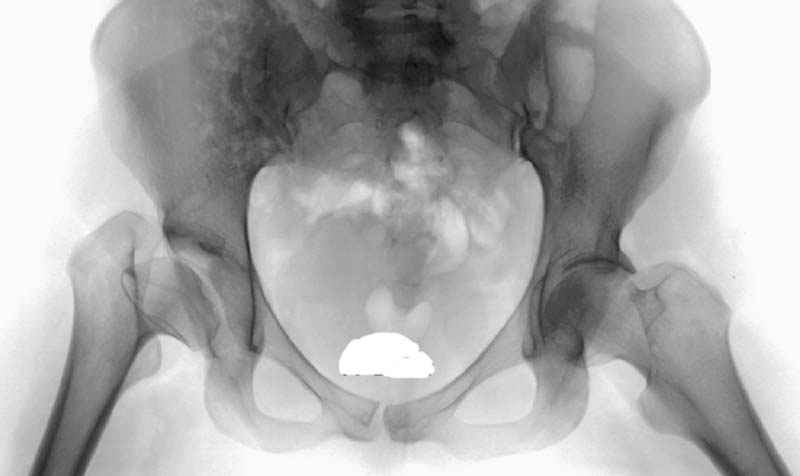

Мною произведены измерения на 290 рентгенограммах ТБС у молодых лиц обоего пола (средний возраст их 26.919 лет) без признаков патологии означенного сустава. Согласно точным расчетам плечо массы тела в среднем составило 107.685 мм (расстояние от центра головки бедренной кости до средней линии тела). Согласно тем же точным расчетам плечо силы реакции связки головки бедра равняется в среднем 35.190 мм (расстояние от центра головки бедренной кости до дна ямки вертлужной впадины, где прикрепляется проксимальный конец связки головки бедра). Соответственно плечо веса тела относится к плечу силы реакции связки головки бедра как 1:3,060, это если быть точным… Я допускаю, что есть проекционные искажения, эффект увеличения изображения на рентгенограмме, погрешности в измерениях, индивидуальная изменчивость размеров, быть может я недостаточное количество суставов обмерил, точку проксимального крепления связки головки бедренной кости на рентгенограмме не видно, а линия действия ОЦМ в одноопорном ортостатическом положении смещается от центра в сторону ТБС на разную величину, обусловленную антропометрическими особенностями и т.д.… именно поэтому в своем сообщении я указал соотношение 1:3, и назвал его приблизительным».

Как рычаг первого рода ТБС функционирует при переходе от двуопорного в одноопорное положение, очень непродолжительное время (в норме). Опять таки в норме, в одноопорном ортостатическом положении, и в средине одноопорного периода шага ТБС – аналог рычага второго рода. При патологии СГБ, ее дисфункции, после эндопротезирования, ТБС постоянно рычаг первого рода, что и приводит к коксартрозу, АНГБК, истиранию полиэтиленового вкладыша вертлужного компонента в верхнем секторе…

Я полностью согласен с Вами что «Очевидно, что при разрыве связки происходит увеличение нагрузки на верхние отделы головки бедра и впадины…» , да хондролиз возникает не сразу, и не всегда бывает развивается коллапс верхнего сектора головки (последствие такого явление, любезно предоставил мне как факт профессор В.П.Волошин см. его отзывы), бывает изначально происходит и китовидная перестройка… т.е. сценариев несколько…